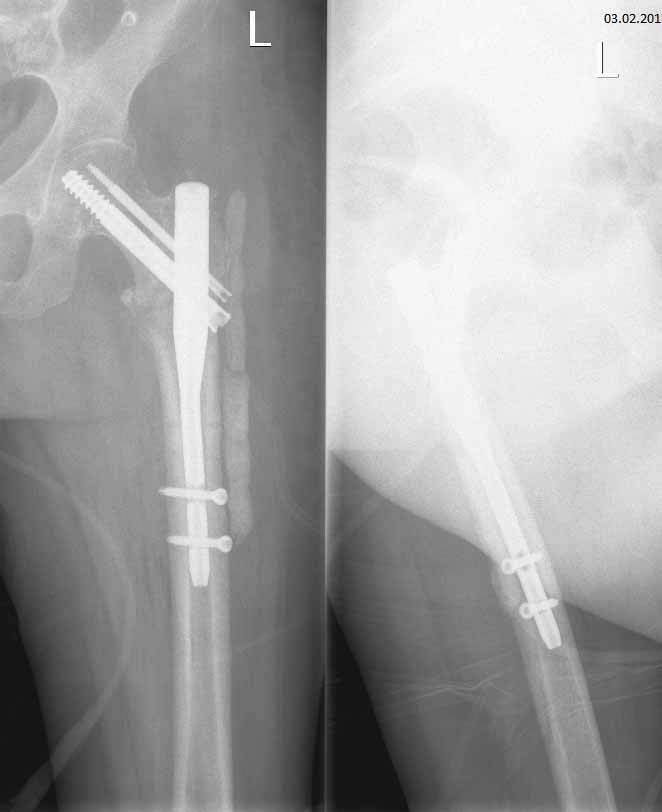

Чрезвертельный перелом левого бедра, в результате ДТП. Женщина 56 лет, ДТП. Чрезвертельный перелом. Было выполнено: скелетное вытяжение- 1 месяц, остеосинтез Г- образной пластиной (Россия), через 4 месяца второй остеосинтез, через 4 месяца вылез винт, выполнена операция- удален один винт, аллопластика. Наложена кокситная повязка. Через 2,5 месяца: щель перелома прослеживается на всем протяжении, склероз по краям отломков. Болей нет. Посоветуйте, что делать дальше, к кому и куда обратиться за помощью. Проживаю в СПб.

Сейчас конструкция несостоятельная. Надо в любом случае ее удалять и заменять на другую, чтобы обеспечить немедленную возможность ходьбы с нагрузкой без риска смещения. Времени на лечение уже ушло в несколько раз больше обычного.

У нас в отделении сейчас делается довольно много операций по такого рода поводам. Предпочли бы сделать остеосинтез стержнем. Есть модификации, исключающие миграцию, подобную случившейся. Делать какие-то пластики и вообще широко обнажать кость не видно необходимости. Возможно, будет целесообразно увеличить шеечно-диафизарный угол.

Технических вариантов несколько, для выбора конкретного варианта надо посмотреть и очно, и предшествующие снимки, и сделать снимок таза с обоими тазобедренными суставами.